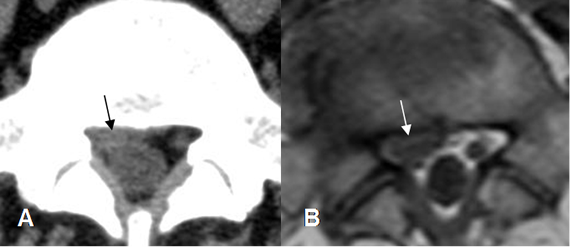

Fig 88. Hernia extruida.

TAC axial: Hernia en el lado izquierdo por debajo del nivel del disco, por fragmento extruido.